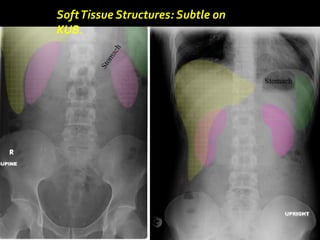

SoftTissue Structures: Subtle on

KUB.